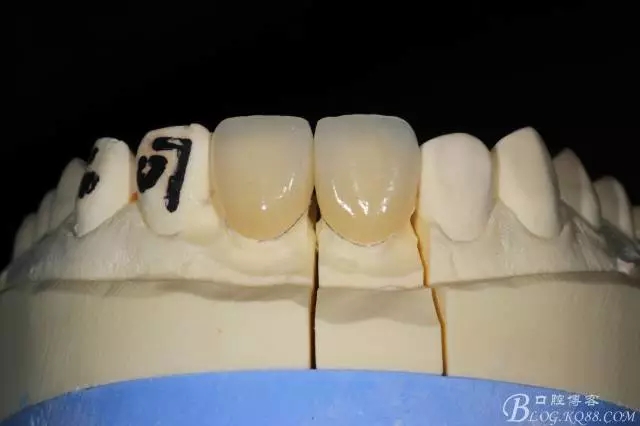

模型上制做完成